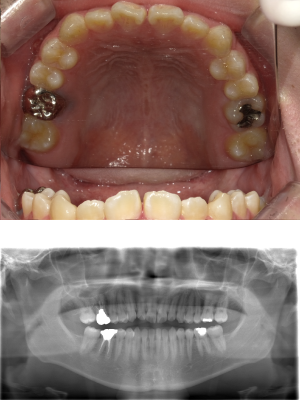

50代 インプラント治療(右上3左上3のみGBR)

| 年代・性別 | 50代・男性 |

| 主訴 | 入れ歯が合わず毎日ヨーグルトしか食べることができないので、しっかり咬めるインプラントにしたい。 |

| 部位 | 右下⑦⑥5④ 上顎③2①①2③ 左下67 |

| 治療期間 | 約9ヶ月 |

| 費用 | ¥4,273,500(税込) |